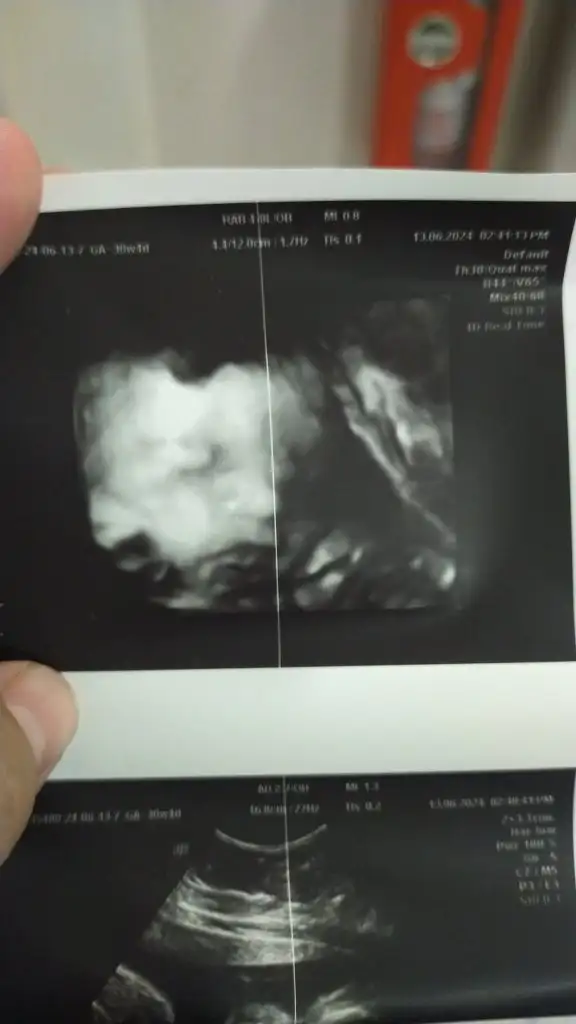

IMG-20240613-WA0005.webp